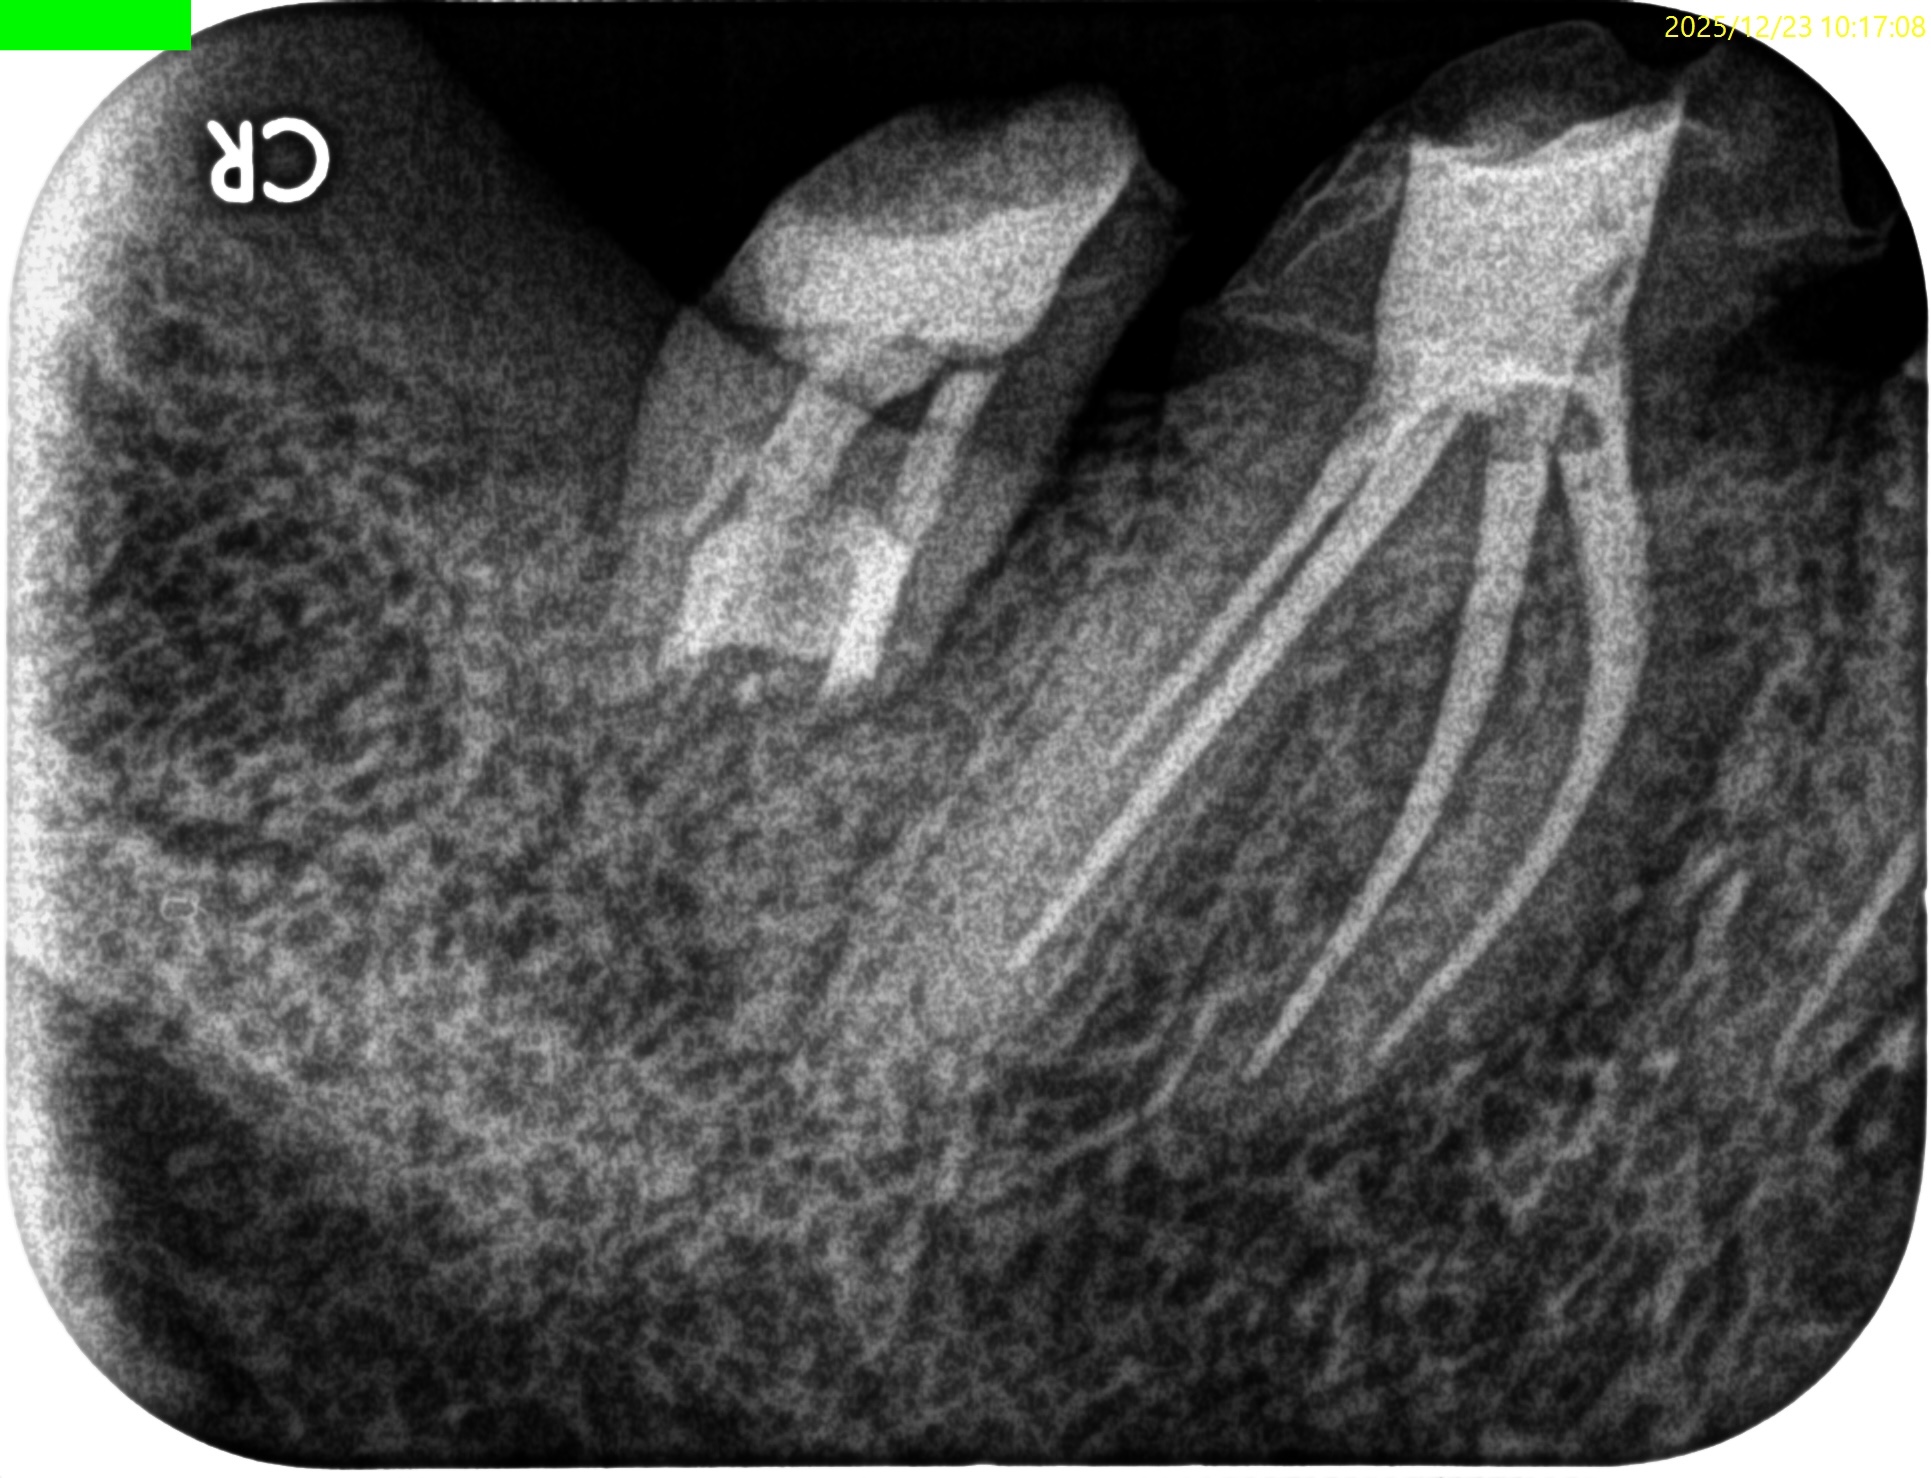

#31 Intentional Replantation 7M recall(2025.12.23)

術前の腫脹、頬側のMBの4mm, Bの6mmの歯周ポケット、歯牙の軽度動揺、咬合痛・圧痛は消失した。

初診時と比較した。

劇的に状態は改善した。